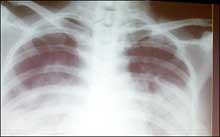

This undated file photo shows a chest X-ray of a SARS victim. Scientists conducting research in eastern China have found that a medicine used to treat schizophrenia is effective in treating patients with the deadly SARS disease. [AFP] |